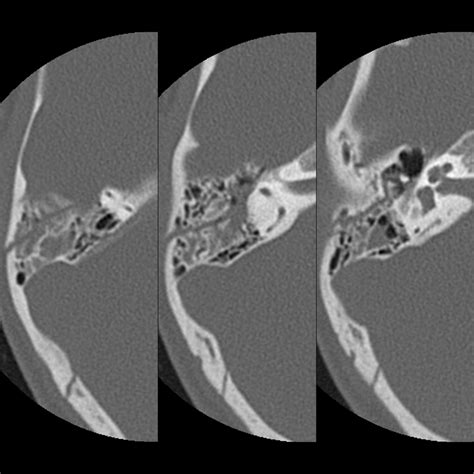

• High-Resolution CT: This technique uses thin slices to capture detailed images of the temporal bone. It is particularly useful for evaluating the bony structures and detecting fractures or erosions.

Interpreting Ct Temporal Bone scans requires a keen eye for detail and a thorough understanding of the temporal bone's anatomy. Here are some key points to consider when interpreting these scans:

Radiologists often use a systematic approach to review Ct Temporal Bone scans, starting with the outer ear and progressing inward to the inner ear structures. This ensures that no abnormalities are missed.